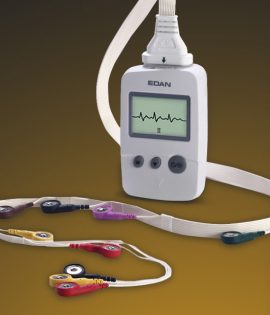

Doppler Fetal de Bolsillo SD1